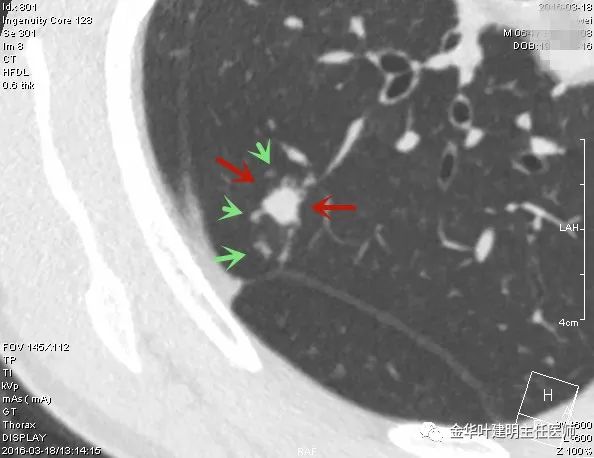

上图示结核。我们发现其有明显的卫星灶,如绿色箭头所示,主病灶处也是周边有模糊区域,病灶整体密度较为均匀(肿瘤容易生长不均致密度欠均匀,显杂乱)。